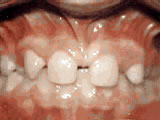

Crowding of the teeth

Patient started treatment at age 11 and wore braces for 26 months. He loves his new smile.